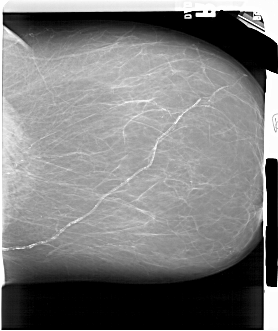

A_1551_1.RIGHT_CC

RIGHT_CC LINES 5941 PIXELS_PER_LINE 4996 BITS_PER_PIXEL 12 RESOLUTION 43.5 NON_OVERLAY